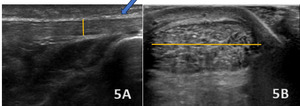

ACHILLES TENDINOPATHY

Figures 5A (LAX View) and 5B (SAX View)

In the LAX view, the Achilles tendon is significantly thickened (highlighted with blue arrow in figure 5A), measuring 10 mm in thickness (highlighted in figure 5A with yellow line) and 24 mm in width (highlighted in figure 5B with yellow line), with hypoechoic areas distributed throughout, indicating degenerative changes. This contrasts with the normal mean values for the Achilles tendon, which are typically 4.94 ± 1.24 mm. The SAX view shows an enlarged cross-sectional area with a rounded or irregular contour, heterogeneous echotexture, and hypoechoic regions, further highlighting the tendinopathic changes.